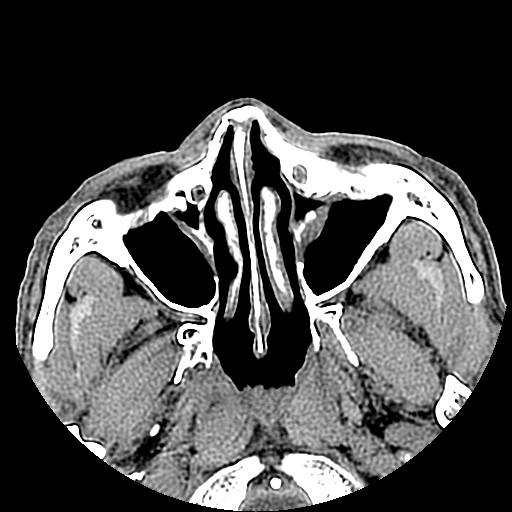

以下是引用liaoqiang在2008-7-16 21:15:00的发言:[br]右侧鼻骨骨折

以下是引用zxd95在2008-7-16 21:39:00的发言:[br]右侧上颌骨额突骨折。[br][br][br][br]